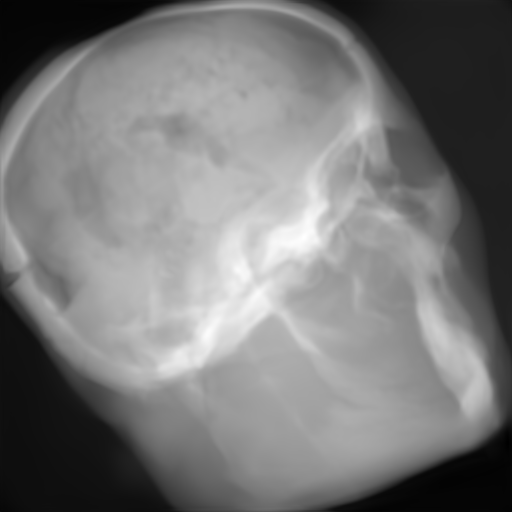

(f) Input: MR proj.

(g) Output: U-net 1subscript1\ell_{1}-loss.

(h) Output: ResNet 1subscript1\ell_{1}-loss.

(i) Output: CRN 1subscript1\ell_{1}-loss.

(j) Reference: X-ray proj.

Figure 2: Results of the projection synthesis. Top row: Results generated with the perceptual-loss function. Bottom row: Results generated with the 1subscript1\ell_{1}-loss function.

The quantitative and qualitative results of the proposed experiments are presented in Table I and Figure 2. By examining these it can be observed that the differences in the calculated MSE of all network architectures and incorporated loss functions are only small. The best results in terms of pixel-wise deviation could be achieved with the ResNet architecture combined with the 1subscript1\ell_{1}-loss function. This network achieves a deviation from the reference of only 0.058, i.e., 2.4 percent. Also the results of the U-net and CRN networks are still good with deviations of 2.6 and 2.9 percent. Similarly small variation can be observed in the structured similarity measure. The ResNet and CRN exhibit approximately equal quality with SSIM measures of 0.938 and 0.920 for the 1subscript1\ell_{1}-loss and 0.924 and 0.931 for the perceptual-loss, respectively. The results generated with the U-net are slightly worse. The highest peak signal-to-noise ratio is achieved by the ResNet (1subscript1\ell_{1}-loss), followed by the U-net (1subscript1\ell_{1}-loss) and CRN (p-loss). It is noteworthy that the ResNet and U-net both achieve the highest results in all error metrics using the 1subscript1\ell_{1}-loss while the opposite is the case for the CRN which works best with the perceptual-loss function.

Overall, the perceptual-loss achieves competitive and in some cases even better results than the 1subscript1\ell_{1}-loss when comparing the pixel-wise error metrics. For example, the cascaded refinement network’s MSE is 0.013 smaller for the perceptual- than for the 1subscript1\ell_{1}-loss. This might be suspicious at first sight, considering that the 1subscript1\ell_{1}-loss purely optimizes for this pixel-wise error in the training process while the perceptual-loss compares the raw feature activations of the evaluation network. Contrarily, this behavior cannot be observed for the U-net and ResNet. The results produced with the 1subscript1\ell_{1}-loss achieve higher values for all error measures for these networks. An explanation for this obervation is that the intensity values of the input image still cause an impact on the respective layers output in the evaluation network when computing the perceptual-loss. Consequently, these differences also transition to the computed loss value for all feature layers. Even though the perceptual-loss incorporates the raw intensity values, it is not guaranteed that the scaling of these is conserved in this process. By this, the relative changes can be similar, whereas the absolute range of values changes and, correspondingly, also the pixel-wise error metrics.

Another observation is that the perceptual-loss is able to conserve high-frequency details in the image. The fine line in the projection images that forms a circle around the cranium is visible in the input (Figures 2a & 2f), as well as in the label images (Figures 2e & 2j), and also in the images generated with the perceptual-loss function (Figures 2b2c, and 2d). In contrast, all generators ”loose” this line when the 11\ell 1-loss is applied (Figures 2g2h, and 2i). This effect is also qualitatively observable in other parts of the images. Despite achieving equal or better results regarding the error metrics, the generally less sharp look of the results generated with the 11\ell 1-loss function is apparent. This behavior is in accordance with previous observations that concluded that an perceptual-loss leads to sharper images than a comparable 11\ell 1-loss [19]. Considering the common applications of X-ray Fluoroscopy, e.g., interventional guidance for stents and similar devices, high spatial resolution is a key requirement. Utilizing a loss function that is able to preserve high-frequency details in the images is desirable to this end. The perceptual-loss appears to be suited for this task as presented in our evaluation.